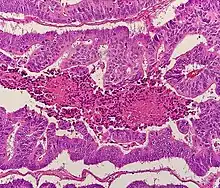

Histopathology

The histopathologic characteristics of the tumor are reported from the analysis of tissue taken from a biopsy or surgery. A pathology report contains a description of the microscopical characteristics of the tumor tissue, including both tumor cells and how the tumor invades into healthy tissues and finally if the tumor appears to be completely removed. The most common form of colon cancer is adenocarcinoma, constituting between 95%[83] and 98%[84] of all cases of colorectal cancer. Other, rarer types include lymphoma, adenosquamous and squamous cell carcinoma. Some subtypes are more aggressive.[85] Immunohistochemistry may be used in uncertain cases.[86]